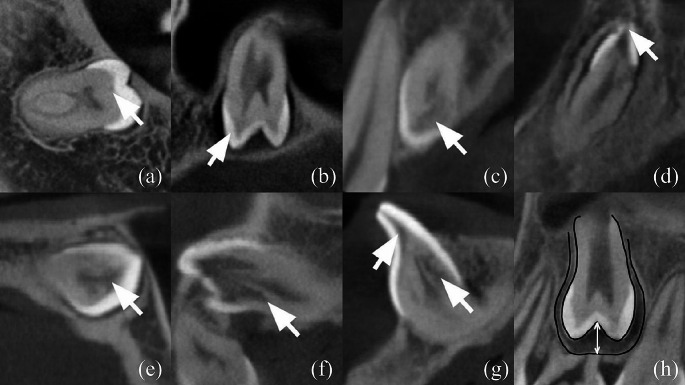

A modified classification of PEIR lesions was employed by combining the classifications proposed by Ozden and Acikgoz et al. and Demirtas et al. [11, 12]. The PEIR score was assigned based on the assessment of the degree of involvement of the crown in a three-dimensional view, as depicted in Fig. 1. The novel classification was introduced depending on the severity of the PEIR lesion as follows: score I indicates the extent of the lesion is less than one-third of the dentinal layer (Fig. 1a), score II denotes the extent of the lesion is between one-third and two-thirds of the dentinal layer (Fig. 1b), score III showing the extent of the lesion is more than two-thirds of the dentinal layer (Fig. 1c), score IV representing the extent of the lesion involves enamel (Fig. 1d), and score V signifying the extent of the lesion involves the pulpal tissue (Fig. 1e). PEIR lesions with higher PEIR scores reflect a higher severity of the lesion.

Fig. 1.

PEIR classification from CBCT images. (a) PEIR Score I, (b) PEIR Score II, (c) PEIR Score III, (d) PEIR Score IV, (e) PEIR Score V, (f) Root Extension, (g) 2 Lesions in 1 Affected Teeth, (h) Distance for Pericoronal Space Measurement